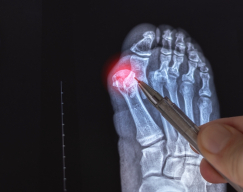

Bunions are one of the most common, and often painful, foot deformities. They are characterized by a bony bump forming on the inside of the big toe. Over time, the deformity can worsen, causing the big toe to angle inward toward the other toes. This leads to discomfort, swelling, difficulty wearing shoes, and in more severe cases, trouble walking or standing for long periods.

Minimally invasive bunion surgery is a modern surgical approach designed to correct the deformity through several very small incisions, usually less than one centimeter. This technique realigns the toe and removes the bony prominence while minimizing disruption to surrounding soft tissue. Compared to traditional open surgery, this method typically results in less swelling, reduced pain, and a faster recovery.